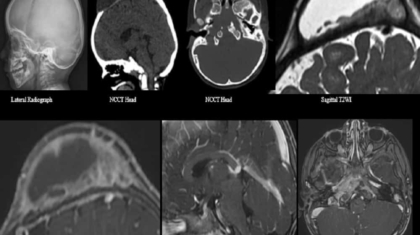

A 3-year-old male presented with nontender gradually progressive cystic swelling over the scalp for 9 months.